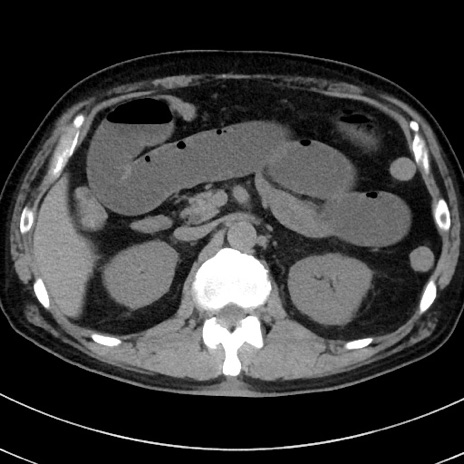

症例38(横断像)

【症例】70歳代 男性

【主訴】腹痛・嘔吐

【現病歴】昨晩より、嘔吐・腹痛あり。今朝になっても嘔吐あり。来院。

【既往歴】心臓バイパス手術、開腹胆摘、腸閉塞

【身体所見】BP 107/71mmHg、HR 116/min、腹部:平坦、軟、下腹部に軽度圧痛あり。反跳痛なし。

【データ】WBC 15100、CRP 0.32